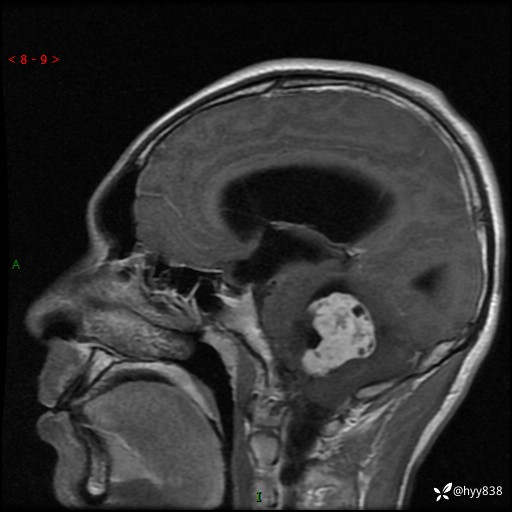

性别:男

年龄:17岁

简要病史:头痛伴间断性呕吐1月余,外院CT提示颅脑占位

颅脑MRI平扫+增强